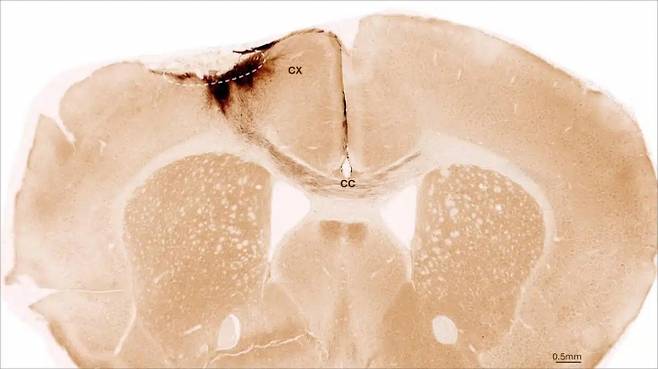

연구진은 신경계의 다양한 세포 유형을 형성할 수 있는 인간 신경줄기세포를 신경전구세포(NPC)라는 특수 뇌세포로 배양해 뇌졸중을 겪은 쥐의 뇌에 이식했다. 실험에 사용된 28마리의 쥐는 인간 줄기세포에 거부 반응을 보이지 않도록 유전자 변형된 상태였다. 28마리 중 11마리에 25만개의 NPC가 투여됐고, 나머지 쥐(대조군 11마리, 위약 대조군 4마리)에는 세포 없이 부형제 용액만 투여됐다.

이식된 세포는 5주 이상 생존했으며 주변 뇌 조직과 상호작용해 치유를 촉진하는 것으로 나타났다. 타켄버그는 “이식된 세포 대부분 뉴런으로 전환돼 이미 존재하는 뇌세포와도 소통하는 것을 확인했다”고 밝혔다.

이식된 세포의 약 78%가 성숙한 뉴런으로 발달했고, 이 중 거의 절반이 GABA성 인터뉴런으로 발달했다. 이는 뇌졸중으로 인해 흔히 소실되며, 지속적인 장애와 관련된 뉴런 유형이다.

치료를 받은 쥐는 손상된 부위의 혈관 성장이 더 강했고, 염증 신호가 감소했으며, 혈액-뇌 장벽 기능이 더 안정적이었다. 또 뇌실하대라는 영역에서 새로운 뉴런을 생성하는 뇌 자체 줄기세포를 자극하는 것으로 나타났다.